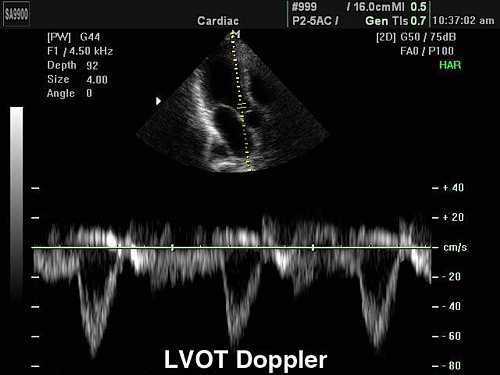

- Измерив выходной тракт ЛЖ и интеграл скорости по времени потока крови в этой области, вычисляют ударный объем и сердечный выброс ЛЖ.

- Импульсно-волновая допплерография позволяет точно локализовать клапанную аномалию (например, различить субаортальный стеноз от аортального и супрааортального), а также (с помощью уравнения непрерывности потока) провести количественную оценку объемов и фракций клапанной регургитации.

- Импульсно-волновая допплерография, с помощью которой можно локализовать место ускорения потока крови. При этом, однако, даже небольшое увеличение скорости кровотока сопровождается появлением феномена разворота допплеровского частотного спектра (артефакт наложения, или алайсинг [aliasing]).

- Постоянно-волновая допплерография, не дающая возможности определить место ускорения кровотока, однако позволяющая правильно идентифицировать высокоскоростные потоки без появления феномена разворота допплеровского частотного спектра (алайсинга).